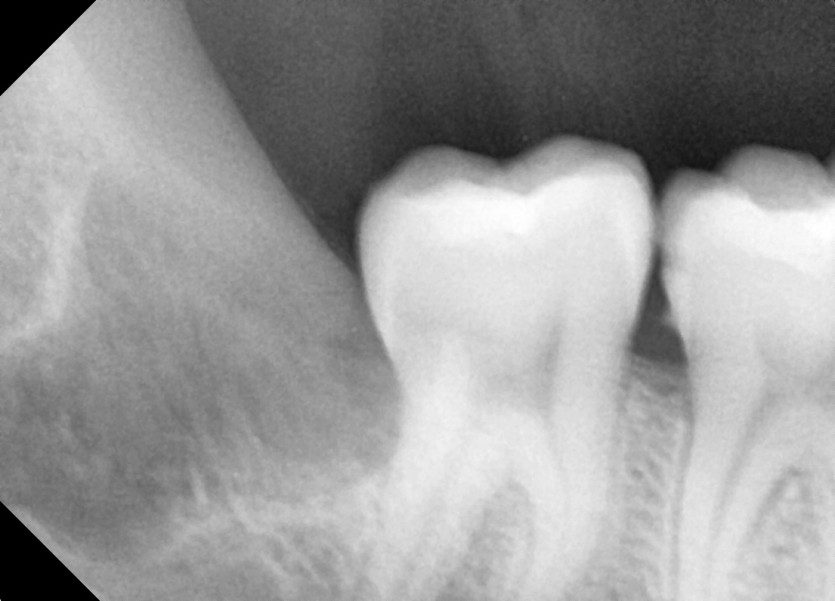

#28,38,48 사랑니 발치

구강 외과 전문의가 당일 발치했습니다.